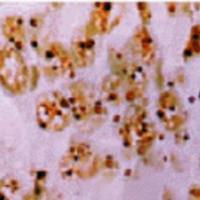

细胞库 / 细胞培养、试剂、耗材、论文服务、技术服务